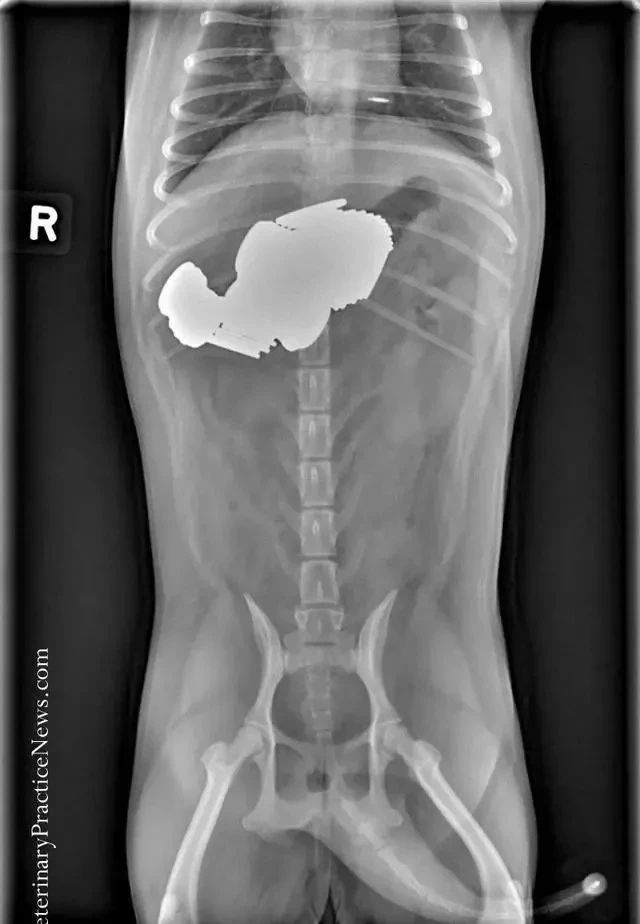

这只狗狗竟然吞下了一只猫......

是的,是只猫!X光影像下狗狗肚子里真的蹲着一只猫。

事实上,这货吞下了好几只猫。

有宠物医院专门PO出了一些X光影像来提醒铲屎官注意狗狗异食行为,看看它们吞下的东西简直让人瞠目结舌。